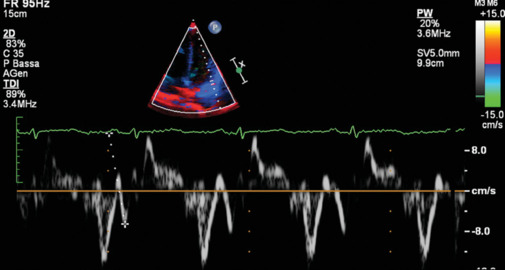

Background: Atrial fibrillation (AF) results in electrical and structural remodeling of the atria, which extent is known to be associated with a higher AF recurrence rate after catheter ablation (CA). Recently, a novel echocardiographic parameter derived from tissue Doppler imaging (TDI) [PA-TDI] has been introduced to assess the total atrial activation time, as a noninvasive surrogate of fibrosis and remodeling. The aim of the study is to investigate the role of PA-TDI interval as a predictor of AF ablation efficacy.

Methods: We retrospectively included patients with paroxysmal symptomatic drug-refractory AF referred to our institution for CA procedure, who presented sinus rhythm at admission. A complete transthoracic echocardiogram was performed before the ablation procedure, including the assessment of PA-TDI interval.